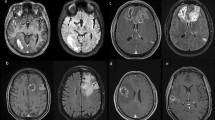

In the treatment of glioblastoma (GBM) the impact of radical tumor resection as first line therapy is beyond controversy. The significance of a second resection in case of tumor-recurrence remains unclear and is an issue of debate. Since GBMs always recur, it is important to determine whether or not patients will benefit from repeat surgery. We performed a retrospective analysis of our prospectively collected database and evaluated all re-resected patients with primary GBM who underwent second surgery during a 3 years period. All patients underwent early postoperative magnetic resonance imaging. We determined survival after re-resection with regard to possible prognostic factors using Kaplan–Meier estimates and Cox regression analyses. Forty patients were included in this study. Median age was 58 years and median KPS score was 80. Average tumor volume was 5.5 cm3. A radiologically confirmed complete resection was achieved in 29 patients (72.5 %). Median follow-up was 18.8 months, and median survival after re-resection was 13.5 months. Only complete removal of contrast enhancing tumor was significantly correlated with survival after re-resection according to multivariate analysis. There was a statistical trend for KPS score influencing survival. In contrast, time between first diagnosis and tumor-recurrence, tumor volume at recurrence, MGMT status and MSM score were not significantly correlated with survival after second surgery. In the event of tumor recurrence, patients in good clinical condition with recurrent GBM amenable to complete resection should thus not be withheld second surgery as a treatment option.